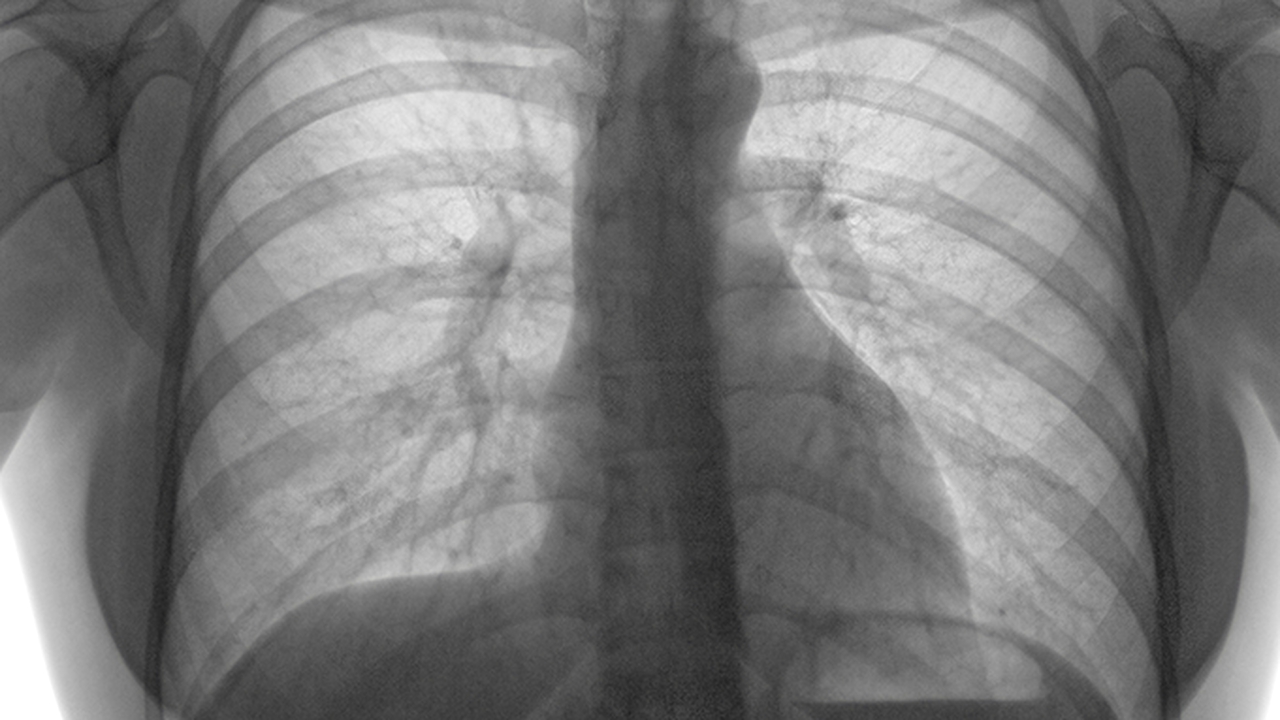

肺结节是一种常见的肺部异常表现,多数为良性,但部分可能为早期肺癌。其成因包括感染、炎症、结核等良性病变,以及肺癌等恶性疾病。早期发现和鉴别诊断对预后至关重要,需结合影像学特征、肿瘤标志物及病理检查综合判断。

肺结节患者应重视定期随访,建议戒烟并避免二手烟暴露。对于直径小于6mm的结节,通常只需年度低剂量CT复查;6-8mm结节需6-12个月随访;大于8mm或有恶性特征的结节应及时专科就诊。保持良好作息、加强锻炼有助于提升肺部免疫力,接触粉尘职业者需做好防护措施。